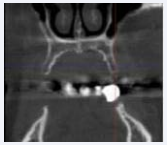

The augmentation in the lower jaw was performed also using a full flap approach and bone grafts from both lineae obliquae (external oblique ridge), which were fixed with titanium screws (Medicon, Unterhaching, Germany) on the residual bone. The bone blocks were covered with xenogenic bone grafting material (BioOss, Geistlich) and membranes (Osseoguard flex, Zimmer Biomet) (Figure 6 a-e).

Figure 6: Augmentation operation in the lower jaw using a full flap and (a) and (b) bone grafts from both lineae obliquae (external oblique ridge), (c) fixed with titanium screws on the residual bone and (d) cover the bone blocks with xenogenic bone grafting material of bovine origin and membranes.